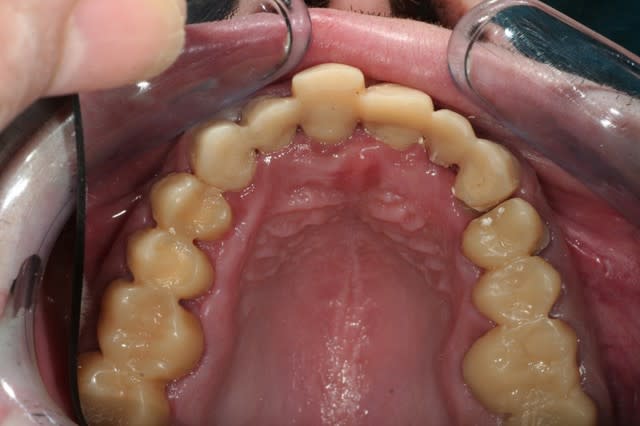

salut les petits clous...

voilà, je me suis remis un peu au boulot.

voici quelques images....

juste une remarque: pour l'instant je suis à la même DV.